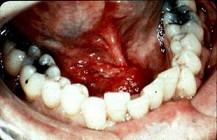

问题 男,40岁,发现右侧口底部有一核桃大小质硬肿块(如图),触诊浸润已过中线。右侧颌下可扪及2个肿大淋巴结,黏连;左侧未扪及明显肿大淋巴结。关于颈部淋巴结的处理,以下哪项最佳()

选项 A.右侧根治性颈淋巴清扫术 B.右侧功能性颈淋巴清扫术 C.右侧根治性颈淋巴清扫术十左侧功能性颈淋巴清扫术 D.双侧根治性颈淋巴清扫术 E.双侧功能性颈淋巴清扫术

答案 C